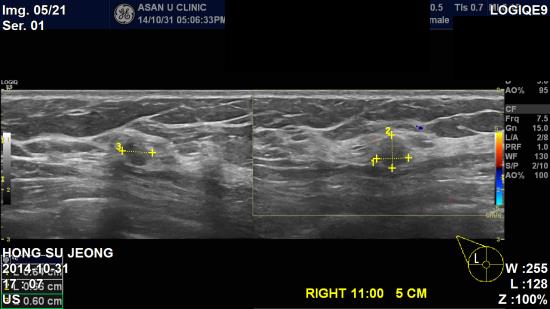

타병원에서 유방 초음파 시행 후 우측 유방 이상소견으로 내원하신 48세 여성분이십니다.

본원에서 유방 초음파 실시하여 우측 유방 11시방향 유두에서 5cm떨어진곳에

0.6cm 작은 혹소견 보여, 조직검사로 침윤성 유관암으로 진단 되었습니다.